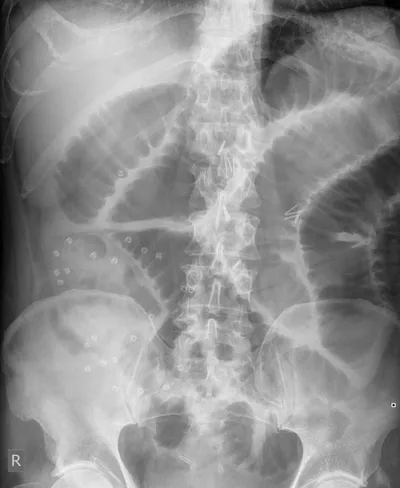

- Permet de rechercher une perforation digestive (pneumopéritoine).

- Permet de rechercher un syndrome occlusif (niveaux hydro-aériques).

- Permet de rechercher une constipation chronique (stase stercorale).

- Permet de rechercher une souffrance digestive (pneumatose pariétale).